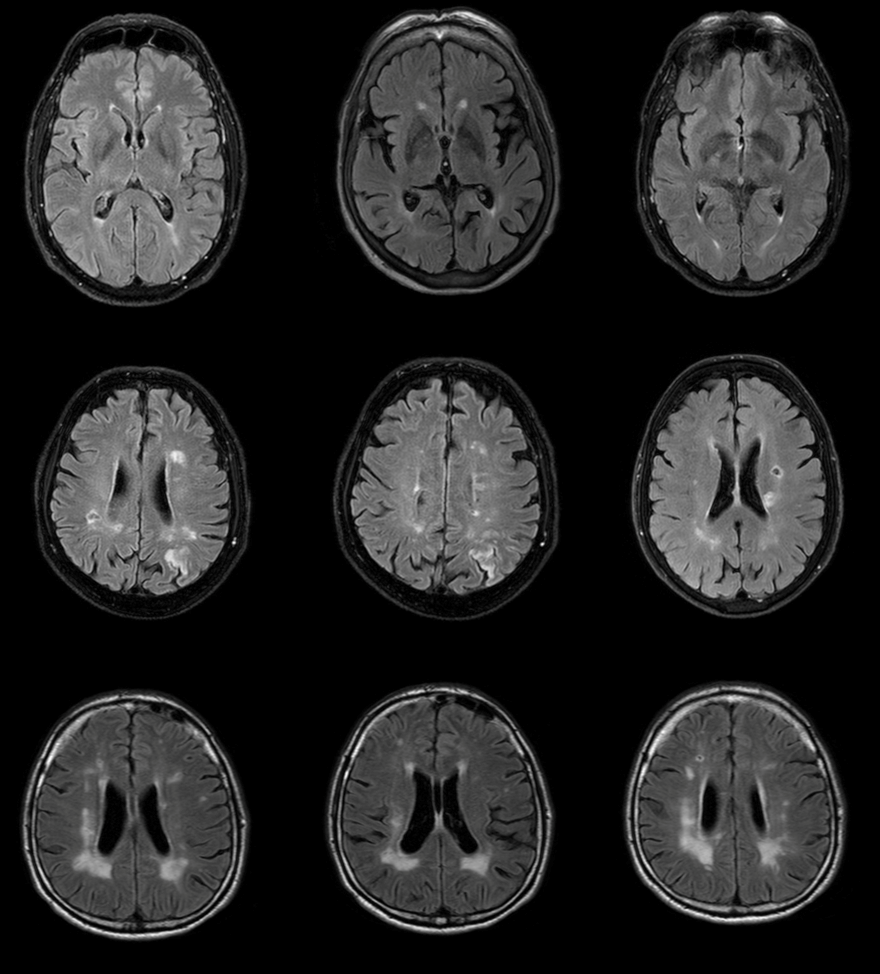

Jako specjalista neurolog zajmuję się diagnostyką i leczeniem przede wszystkim stwardnienia rozsianego oraz innych chorób demielinizacyjnych, a także migreny i innych bólów głowy.